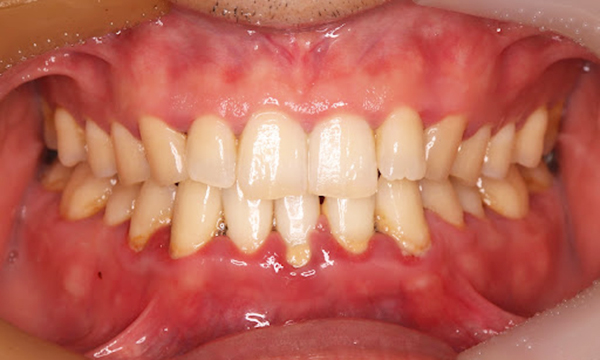

Before

症例

after

基本情報

年齢・性別 41歳・男性

主訴 主訴:歯ぐきから出血する

治療部位:全顎

治療内容 1.歯周ポケット検査、資料取り(レントゲン写真14枚・口腔内写真)、歯磨き指導

2.歯磨き指導チェック、縁上の歯石除去

3.縁下の歯石除去4回

4.再評価(歯周ポケット検査・レントゲン写真14枚・口腔内写真)

5.メインテナンス

治療期間 1日

治療費 合計:14,160円

内訳(全て保険診療3割負担)

・初診検査、歯磨き指導、縁上の歯石除去:3,630円

・レントゲン写真、縁下の歯石除去①:3,040円

・縁下の歯石除去②:1,530円

・歯磨き指導チェック、縁下の歯石除去③:2,070円

・縁下の歯石除去④:1,530円

・再評価:2,360円

(2022年5月現在現在)

リスク・副作用 ・歯石除去後すぐは歯ぐきを触っているため歯ぐきに違和感や痛みを感じる場合がある

・歯石除去により今まで腫れていた歯ぐきが引き締まり歯ぐきが下がる可能性がある

・歯ぐきが引き締まって下がることにより歯面が今までより露出し知覚過敏の症状がでる可能性がある

・歯石除去後、歯磨きを怠ると細菌が歯周ポケットのより深部まで入ってしまうため歯周病が悪化してしまう可能性がある

・一度歯周病になると再発しやすい為、定期的なメインテナンスが必要になります

治療方針 1.歯磨き指導

2.歯ぐき上の歯石除去

3.歯ぐき下の歯石除去

4.再評価

5.定期的なメインテナンス

特記事項 ・着色除去(PMTC)は自費治療のため希望しませんでした。

・右下7番の歯周ポケット5mmは親知らずの関係もあり、このまま維持していくことを説明しています。

・他4mmの歯周ポケットに関しては歯垢が少し残っていた為、再度歯磨き指導と、縁下の歯石を確認して様子をみることにしました。

担当者所見 全体的に出血が見られたのと、奥の歯ぐきは炎症があり歯周ポケットが深かった為、まずは歯ブラシの当て方+歯間ブラシ3Sサイズを使用して頂き炎症を落ち着かせました。

両方毎日使用して頂いた為、スムーズに歯周病治療を行うことができました。毎日のホームケアが不十分だと、なかなか結果に繋がらず、治療期間も長くかかってしまう為、患者様の協力が歯周病治療を成功させるためにはかなり重要になっていきます。

そして一度病気になった歯ぐきは再発しやすい為、今後は3ヶ月に1度の定期的なメインテナンスで、この状態を維持できるよう一緒に管理していきます。